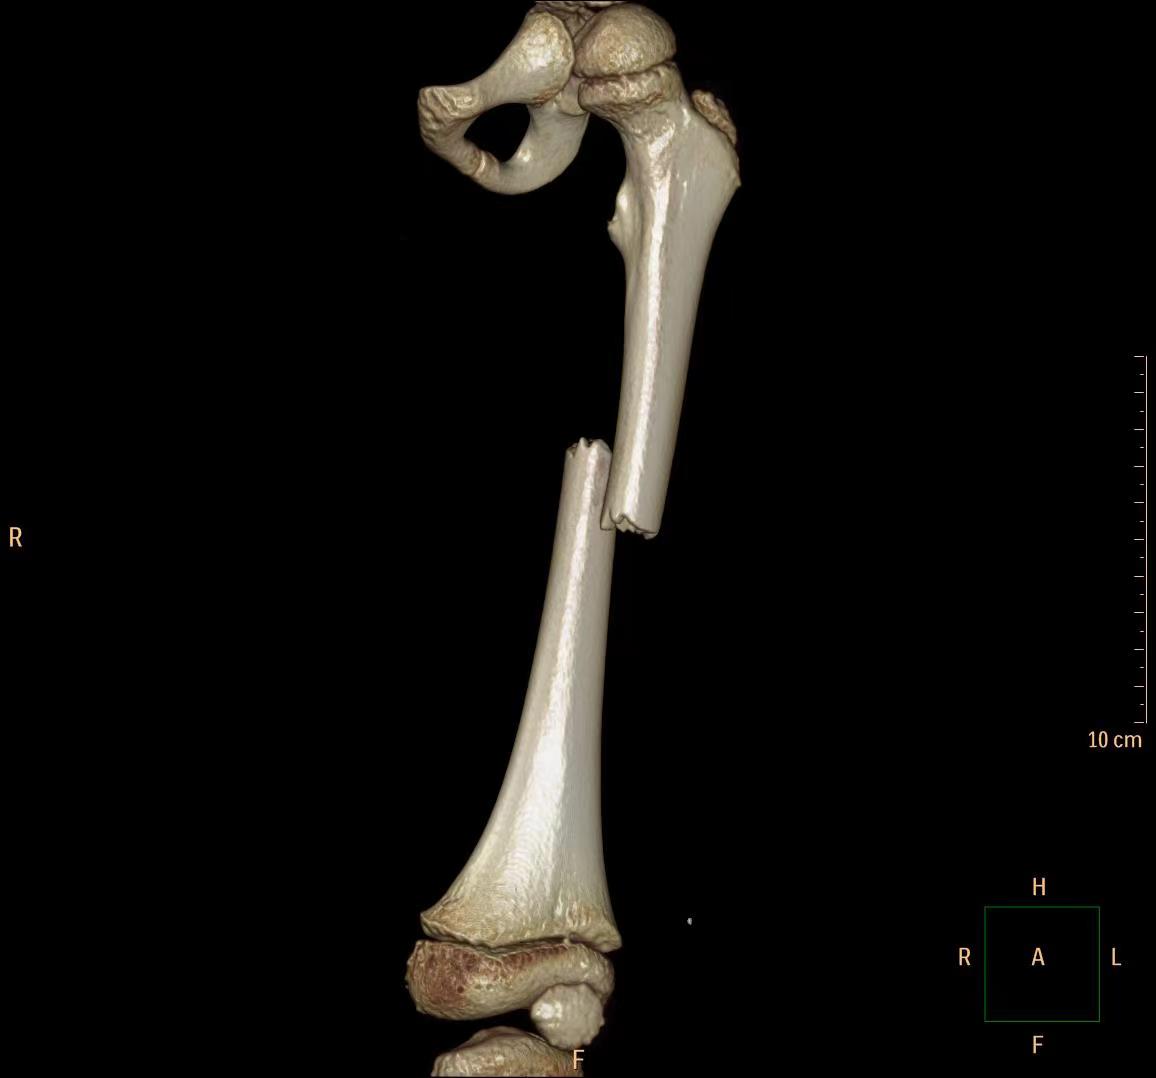

完善各项术前准备工作后,在李杨主任指导下由袁岭副主任医师主刀,开始为患儿实施左股骨干骨折微创撬拨复位弹性髓内针内固定手术。术中,医生通过股骨远端两个约1cm手术切口,将两枚弹性髓内针精准置入股骨髓腔内,顺利完成了复位和固定。乐乐骨折部位仅留下一个直径约0.5cm大小的撬拨复位通道,手术时间短,术中出血量极少,术后骨折即刻得到稳定,在半髋肢具或石膏保护下,术后患肢很快就能进行不负重功能训练,护理非常方便,复查骨折断端对位对线良好,畸形纠正。全家人都对湘南学院附属医院骨二科团队感到非常满意,乐乐顺利康复出院的当天,乐乐奶奶对医务人员激动地说:“我孙子是不幸从楼上掉下来,幸运的是碰到了这么优秀的医师团队,真的非常感谢您们!”